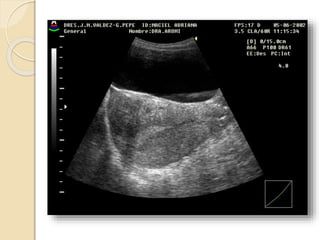

Útero púber: 7cm. 5cm. 4cm

Tamaño: Útero prepúber:3 cm. 1 cm. 1 cm En esta fase el cuerpo y el cuello uterino tienen una longitud similar dando un índice cuerpo-cuello de 1-1 o 1-2 a favor del cérvix